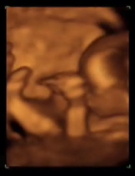

La ecografía de la semana 12 se realiza cuándo la medida del embrión, tomada desde la cabeza a la rabadilla [ Ver ecografía bidimensional ], está entre 45 y 84 milímetros. Esto se corresponde con un embarazo comprendido entre las semanas 11 y 13,6, contadas desde el primer día de la última regla.

El aspecto, sobre todo a partir de la semana 12, es parecido al de un recién nacido [ Ver ecografía en 3D ]. Se pueden distinguir con claridad la cabeza, el tórax, el abdomen y las extremidades. El embrión está rodeado de una cantidad abundante de líquido amniótico, es bastante móvil y tiene tendencia a apoyar la espalda sobre la cara posterior del útero, lo que nos facilita las mediciones.